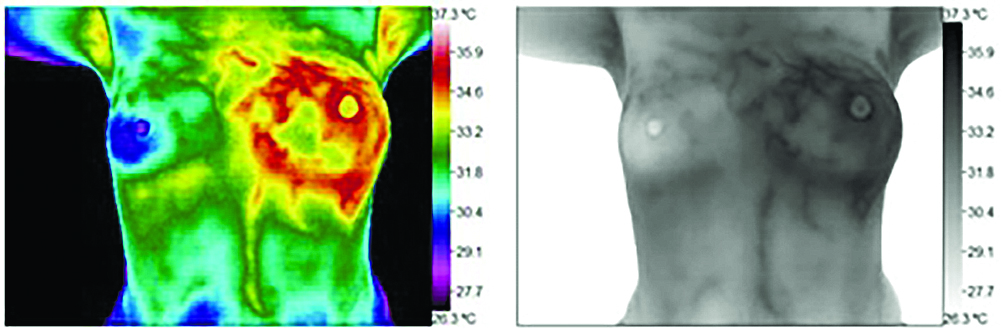

Термография представляет собой современную процедуру скрининга без радиации, которая использует детектор тепла для определения областей разницы температур в теле.

Большинство патологических процессов демонстрируют «форму повышенной жары», а некоторые неврологические процессы показывают чрезмерный холод или переохлаждение

Заболевание молочной железы может быть выявлено путем поиска областей избыточной или повышенной температуры, которые могут указывать на области ангиогенеза или увеличения кровеносных сосудов, снабжаемых растущей опухолью.

Термография используется для выявления рака молочной железы в Соединенных Штатах с 1956 года. Она была одобрена FDA в 1982 году. В рецензируемых журналах опубликовано более 800 исследований, посвященных термографии только одной молочной железы.

Большинство этих статей показывают успешность применения термографии молочной железы более 90% случаев. Так, исследование 2008 года в Нью-Йоркской пресвитерианской больнице в Корнеле, опубликованное в Americal Journal of Surgery, показало точность обнаружения на 97%.